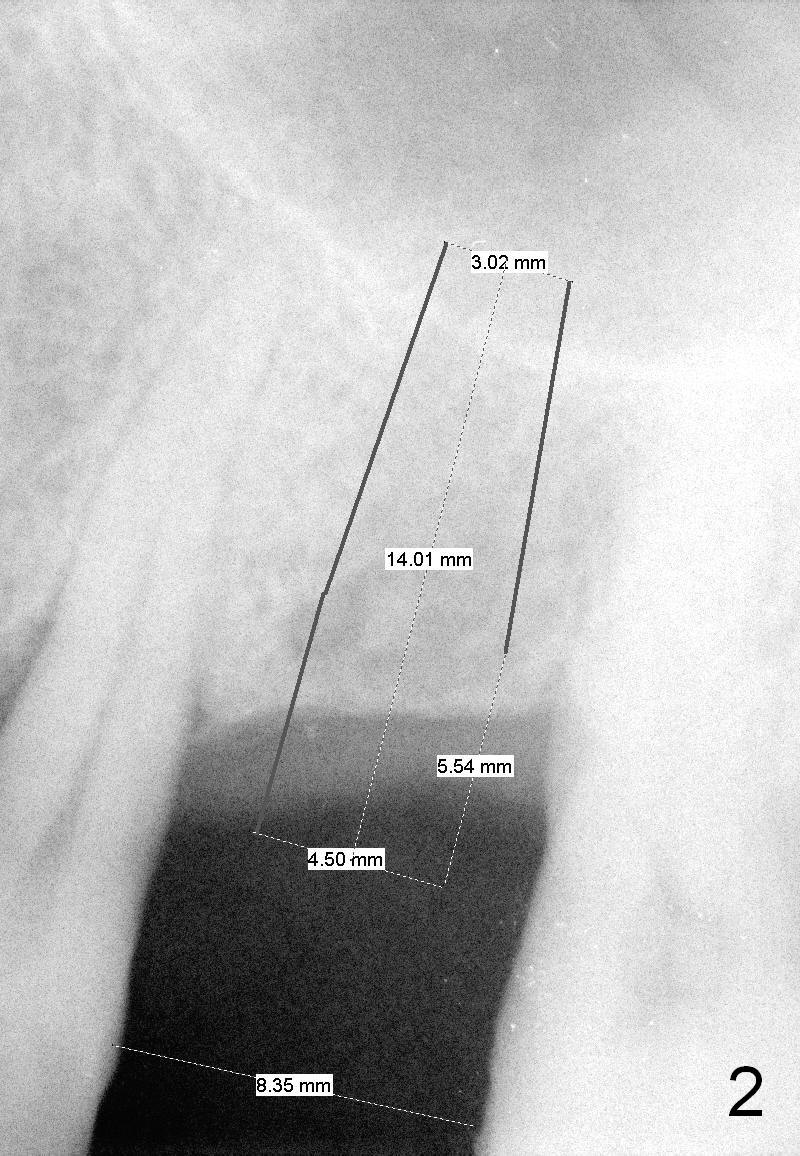

Although the edentulous space is not narrow at #10 (Fig.4), a small diameter implant should be used due to anterior diastemata (Fig.5). The implant will be placed slightly mesially to have a diastema distally (Fig.6 *). If there is a labial apical concavity, a shorter implant will be placed (14 mm). Also prepare angled 1-piece implants. Take preop photos to show the labial concavity if present.